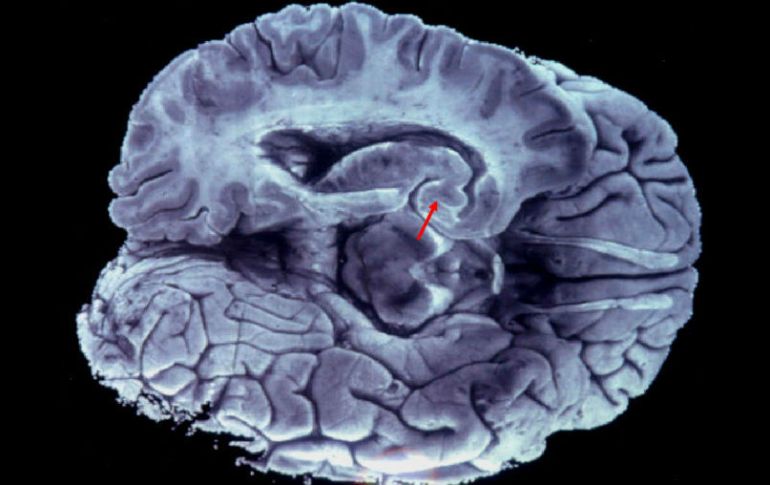

Tecnología | Se busca disminuir padecimientos neuronales a través de impulsos electromagnéticos Pretenden 'hackear' el cerebro para curar males Se busca disminuir padecimientos neuronales a través de impulsos electromagnéticos Por: SUN 19 de julio de 2015 - 11:28 hs El proceso trata de generar conexiones entre las redes que conforman los 86 mil millones de neuronas que hay en el órgano. EL INFORMADOR / ARCHIVO CIUDAD DE MÉXICO (19/JUL/2015).- La Secretaría de Ciencia, Tecnología e Innovación busca hackear el cerebro humano a través de impulsos electromagnéticos para disminuir padecimientos como el dolor crónico, ayudar en la recuperación del habla en pacientes con infartos cerebrales y reducir los efectos del Parkinson. A través de aparatos de Estimulación Magnética Transcraneal Repetitiva, la Seciti y la Secretaría de Salud del DF colaboran en la Clínica de Transtornos y Movimientos del Sueño dando tratamiento a personas con transtornos neuronales. A través de la aplicación de campos magnéticos controlados, los pacientes han podido disminuir dolores por neuropatías y migrañas y está en fase de prueba para la reducción de los efectos del mal de Parkinson, lo cual pudiera darle a los pacientes la posibilidad de alejar el tiempo en el que inicia su periodo de medicación, mejorando su calidad de vida. Según el titular de la Secretaría de Ciencia Tecnología e Innovación ( Seciti), René Drucker, la red médica del Distrito Federal es la única que cuenta con este equipo de reciente creación ya que cada máquina tiene un valor millonario y aunque en otros hospitales privados existen aparatos similares, ninguno tiene la tecnología que poseen las cuatro máquinas instaladas en el Hospital Ajusco Medio. En cuanto a su funcionamiento, Carlos David Castillo, especialista en neurología y neurofisiología, explicó que no se trata de imanes ni chacras como muchos dicen, sino de generar campos magnéticos controlados que den destellos de energía a las neuronas y sea posible encenderlas y apagarlas a voluntad. “Es como hackear el cerebro y más allá de encender o inhibir neuronas se trata de generar conexiones entre las redes que conforman los 86 mil millones de neuronas que cada persona tiene empacadas en el cerebro”, dijo. El doctor Castillo indicó que cuando se encienden y apagan neuronas de manera repetitiva, a lo largo de los días se pueden crear o inhibir conexiones y así dar tratamiento a enfermedades que antes no lo tenían. “Hay cosas para las que sabemos que la terapia Electromagnética Transcreanal Repetitiva funciona, por ejemplo, la depresión refractaria, rehabilitación tras infartos cerebrales, el dolor crónico neuropático”. Para acceder a este nivel de atención es necesario acudir a los Centros de Salud de la ciudad de México. Temas Investigación científica Ciencia médica Cerebro Mal de Parkinson Neurología Lee También Estudio chino revela una mutación que eleva riesgo de alzhéimer NASA confirma si el cometa 31/ATLAS amenaza la vida en la Tierra o no Detalles sobre la esquizofrenia, la experiencia de "voces" internas Conmociones cerebrales, la cuarta lesión más frecuente en partidos de la Conmebol Recibe las últimas noticias en tu e-mail Todo lo que necesitas saber para comenzar tu día Registrarse implica aceptar los Términos y Condiciones